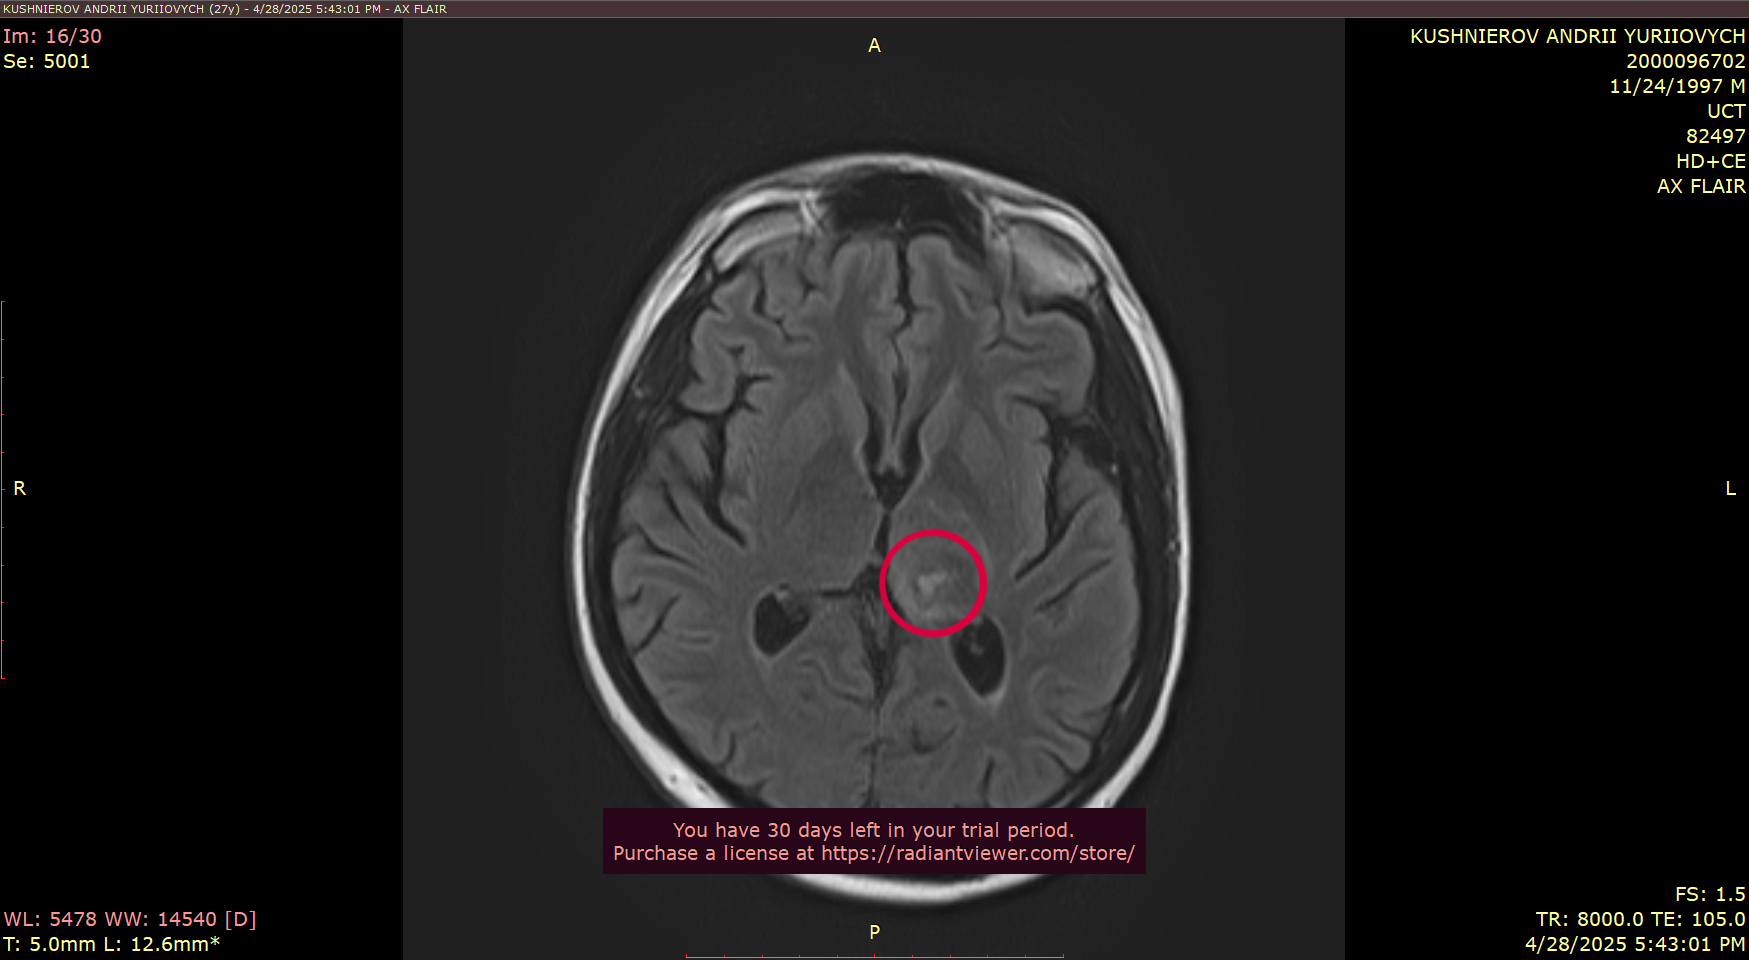

As some are aware - he was diagnosed last year with glioblastoma, an aggressive cancer of the brain and many in the community helped to fund his biopsy.

As many of you know, I’ve been battling glioblastoma — an aggressive form of brain cancer. Over the past year, I underwent 12 months of chemotherapy, hoping it would stop the tumor’s growth. Unfortunately, it hasn’t helped. The situation has become critical.

The location of the tumor in the brain makes the tumor almost inoperable, because of the high risk of being paralyzed — but now my condition has worsened, and emergency brain surgery must be done very soon, likely next week, here in Ukraine to address the immediate threat. This surgery won’t heal me, but it’s necessary to stabilize my condition. After that, I must travel to Germany for more advanced treatment and another surgery, which may allow doctors to remove a larger portion of the tumor and offer a better chance at extending my life.

Description of MRI scan results. Scan images are included above.